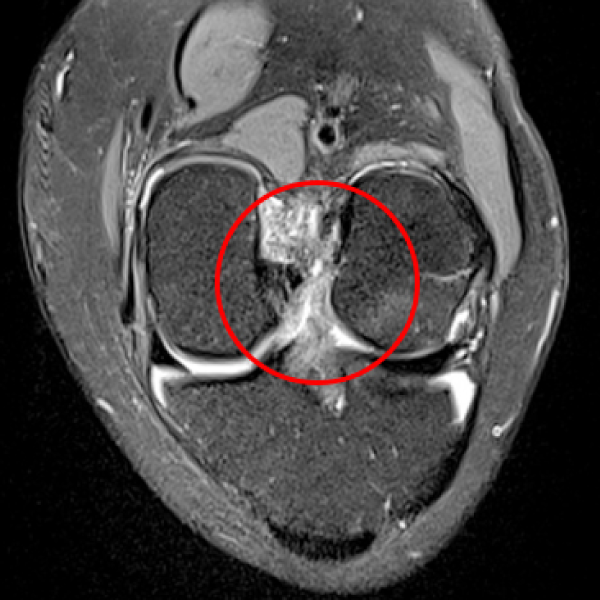

십자인대가 파열되어 하얗게 보임

2020.09.08